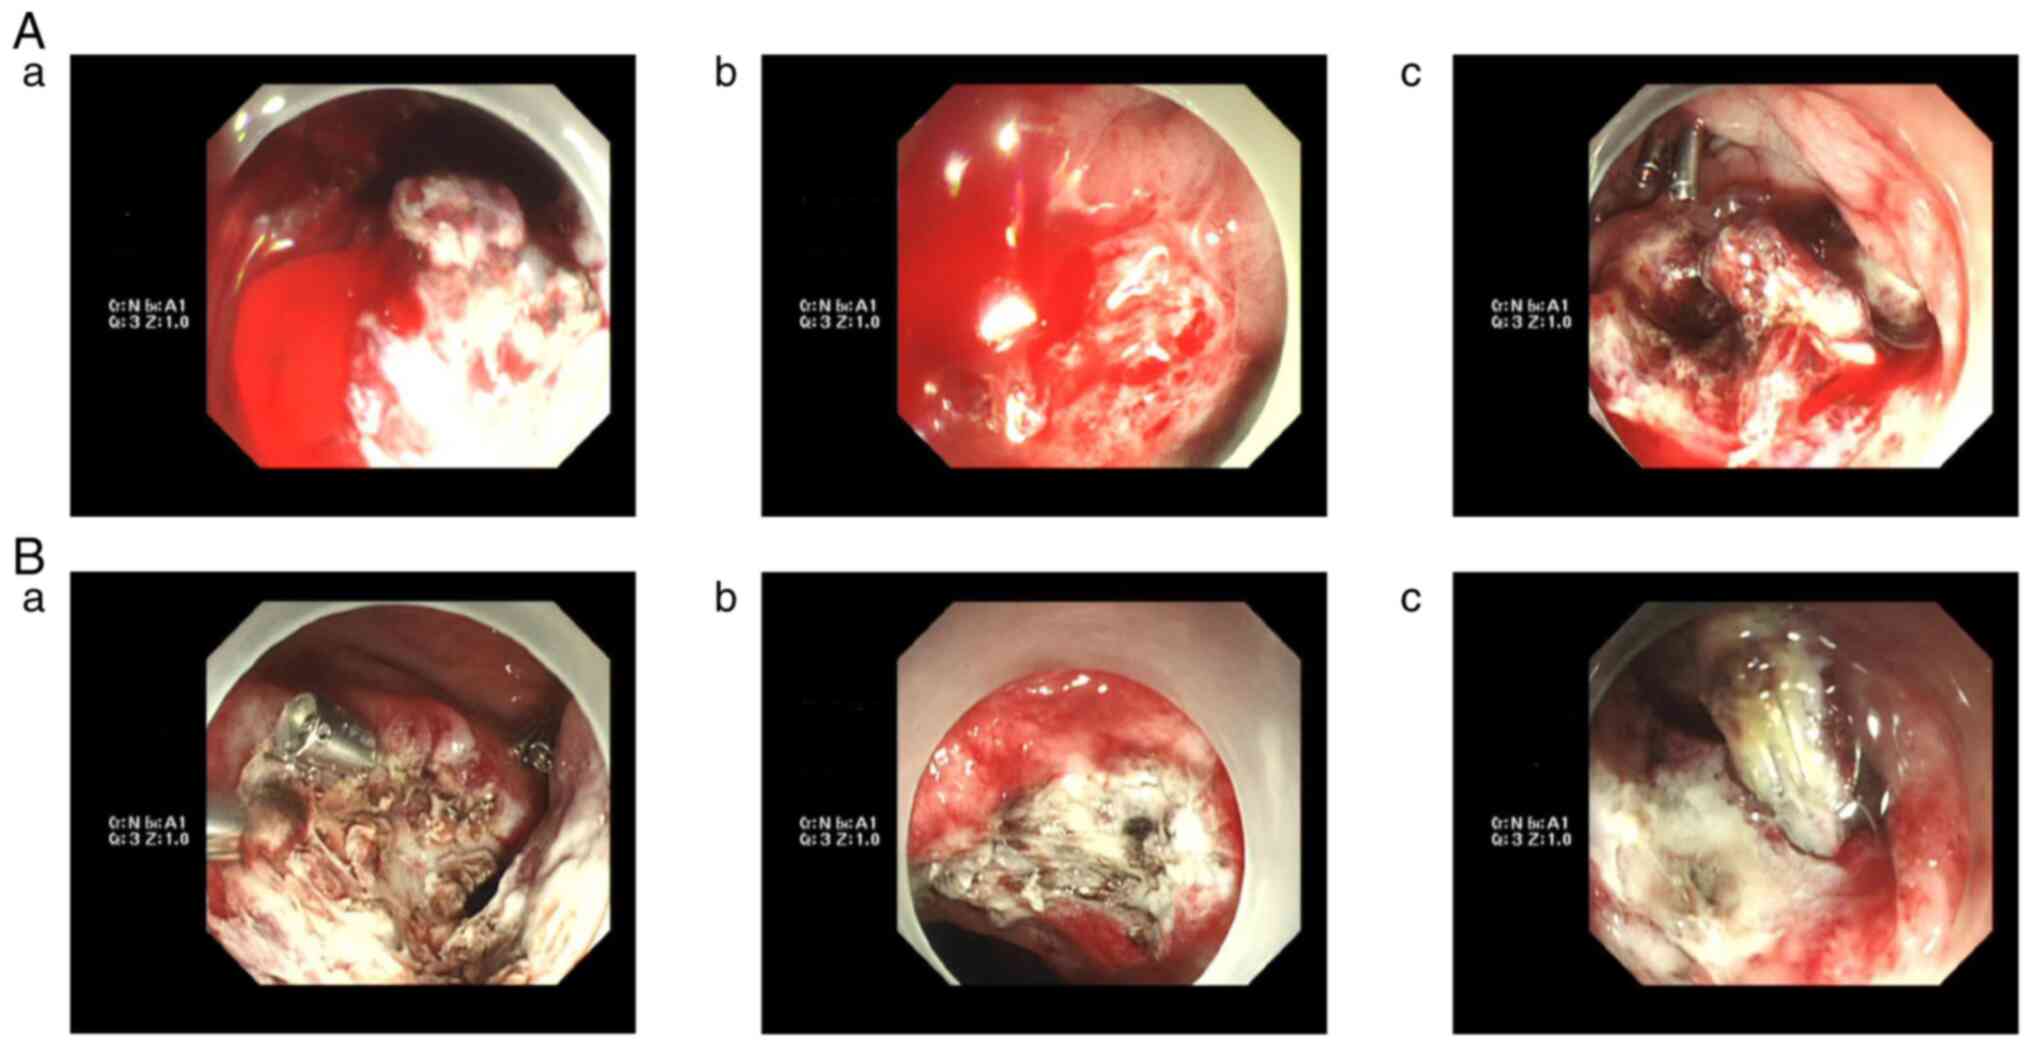

Figure 4

Endoscopic hemostasis process. (A-a) The third postoperative hemorrhage. (B-a) The third electrocoagulation hemostasis and titanium clip hemostasis. (A-b) The fifth postoperative hemorrhage. (B-b) The fifth electrocoagulation hemostasis. (A-c) The seventh postoperative hemorrhage. (B-c) The seventh electrocoagulation hemostasis.